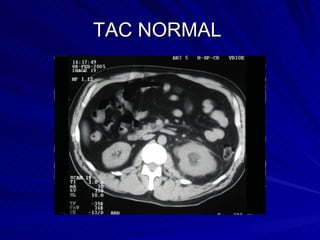

TAC NORMAL